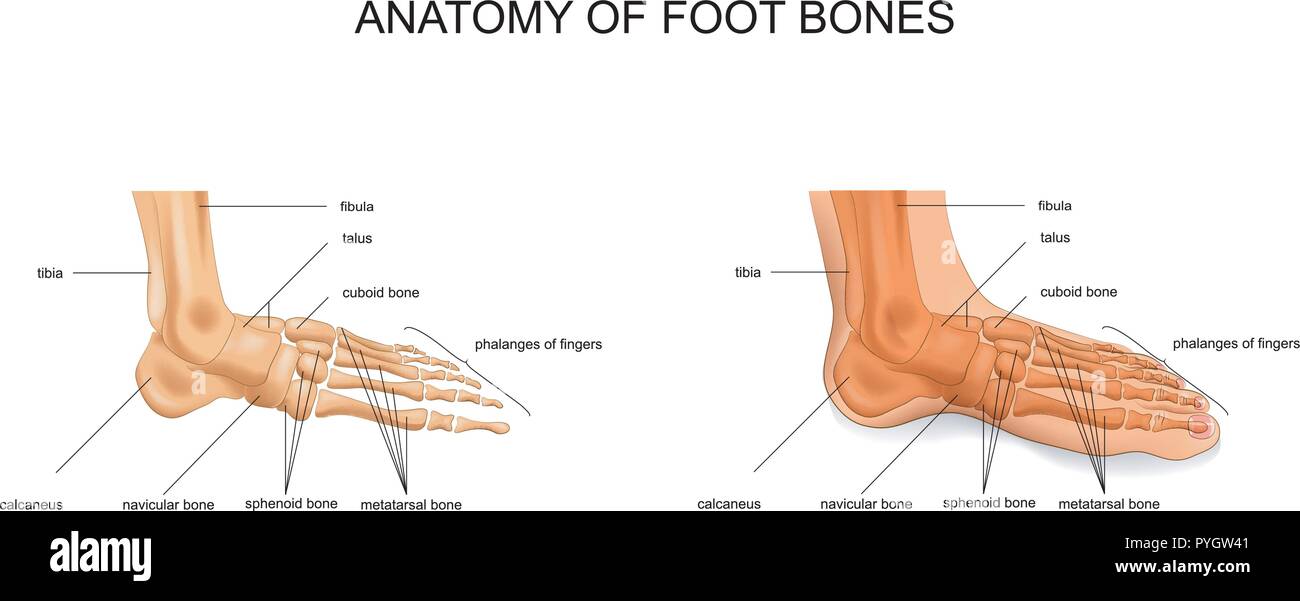

RF2DHMD0H–OS du pied. Anatomie humaine. Le schéma montre l'emplacement et le nom de tous les os du pied.

RMK228DY–Partie terminale du membre inférieur, reposant sur le sol au cours de posture droite ; le squelette du pied a 26 os.

RMK227XM–Partie terminale du membre inférieur, reposant sur le sol au cours de posture droite ; le squelette du pied a 26 os.